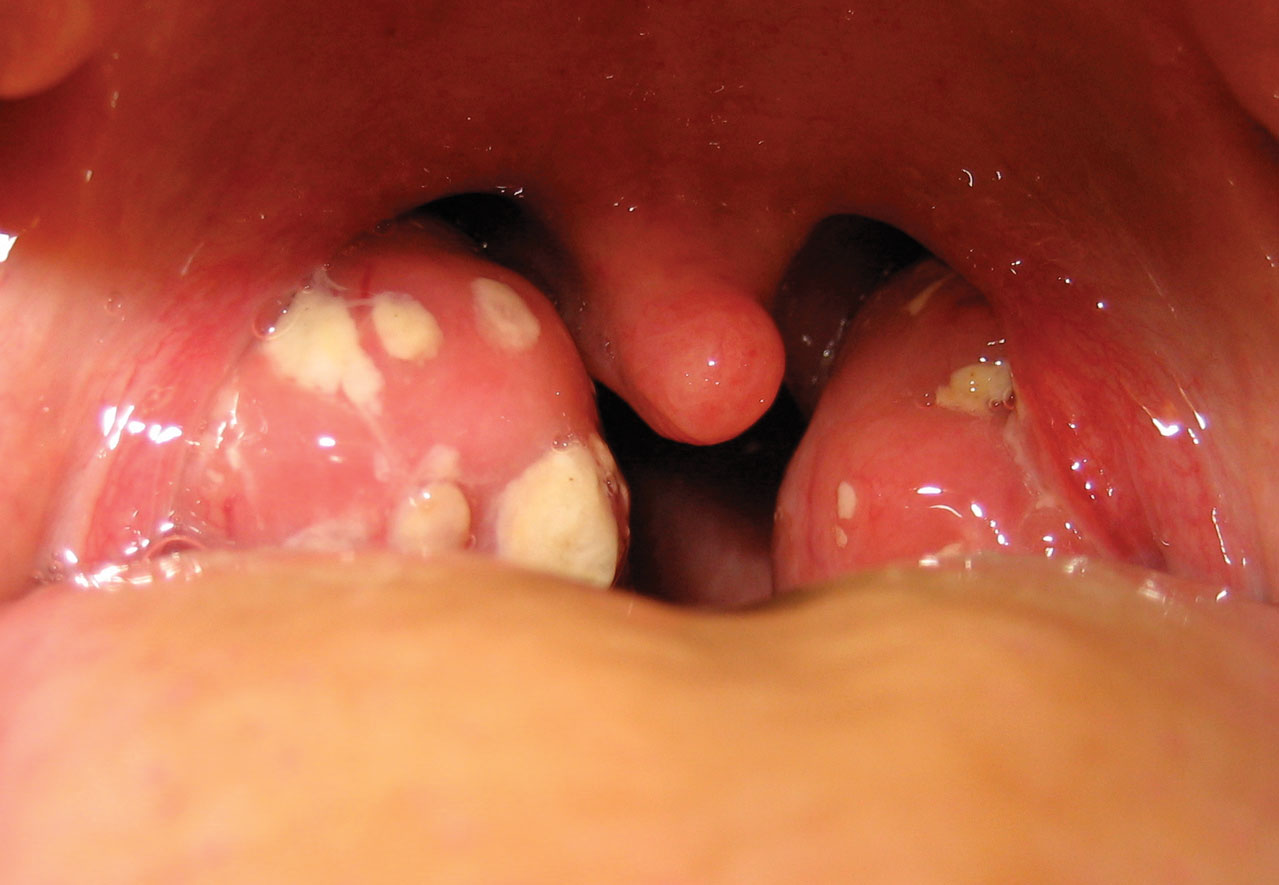

Tonsillitis is an infection of the tonsils. Tonsils are lumps of tissue on both sides of the back of the throat that help the immune system protect the body from infections. Inflamed tonsils get red and swollen and can cause a sore throat.

Inflamed tonsils look red and swollen, and may be covered with a yellow or whitish coating or spots. A child with tonsillitis may have: